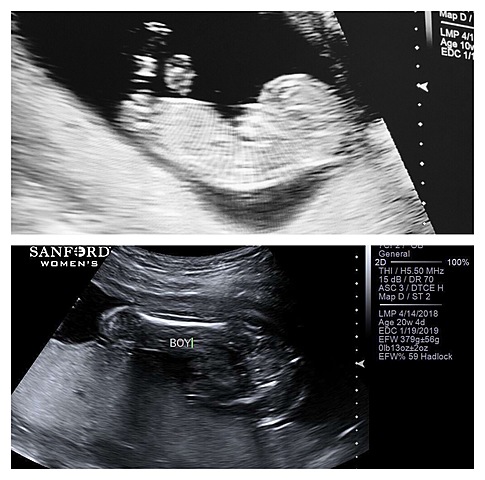

It's a boy!

This day was very exciting for sure! I wish we would have done a gender reveal but sadly we didn't. On my Instagram page, I put a pull up. The pull was "what do you think it will be?!" and you got to guess boy or girl. After I found out, I posted a picture from that ultrasound and captioned it, " a baby boy full of joy". Everyone was so excited!!